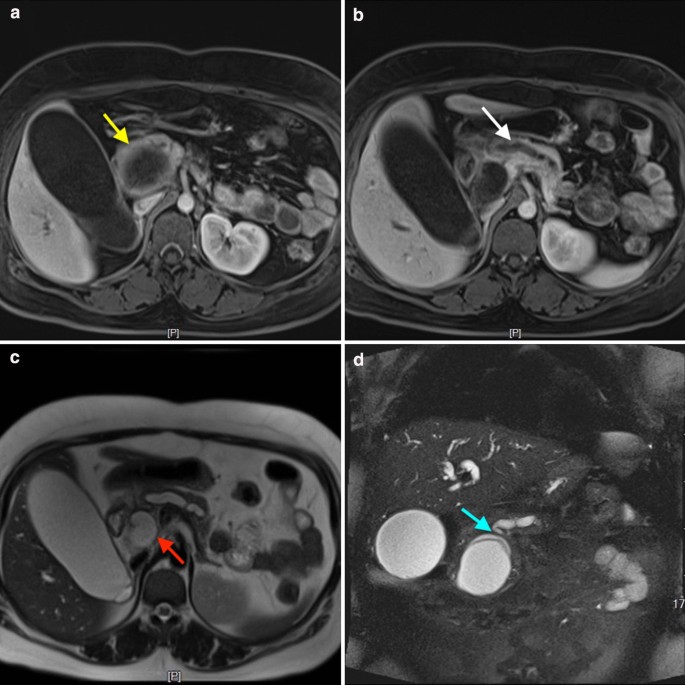

A 28-year-old woman presented to our department with body itching for more than ten days and jaundice for nine days. This patient had a long-term history of living in an area in which echinococcosis is endemic. Medical examination demonstrated yellow discoloration in both the skin and sclera, and abdominal examination was negative. After admission, the laboratory tests indicated a serum total bilirubin (Tbil) level of 264.0 μmol/L (5–22 μmol/L), conjugated bilirubin (Dbil) level of 205.6 μmol/L (0–7 μmol/L) and unconjugated bilirubin (Ibil) level of 58.4 μmol/L (0–20 μmol/L). Serum tumor markers, including carbohydrate antigen 19–9, α-fetoprotein and carcinoembryonic antigen, were not present. On the imaging examination, an emergency computed tomography (CT) scan indicated a 6.0 × 5.3 cm cystic lesion in the head of the pancreas adjacent to the lower bile duct and main pancreatic duct that induced expansion. There were no solid nodules or calcifications in this lesion, and a slightly higher lesion density with a curved mild calcification was observed at the edge of the cyst (Fig. 1). Magnetic resonance imaging (MRI) indicated the same signals at the center of the lesion and a high signal around the wall of the capsule, suggesting local diffusion limitation. MRCP imaging demonstrated that the bile duct and main pancreatic duct were clearly dilated, and the cyst communicated with the pancreatic bile duct (Fig. 2). Based on the preoperative examination, a diagnosis of pancreatic cystadenoma was made.

Enhancing CT scans, MRI and/or contrast-enhanced ultrasound examinations facilitate diagnosis. The characteristics of signals or multiple subcysts, calcifications and consolidation may be present in the resulting images. Kerimoglu et al. demonstrated that mild enhancement of the medial edge of the capsule wall might occur [30]. In our case, the image of the pancreatic tail shows a single capsule with a clear boundary. The cross-section image shows local nodular thickening of the cystic wall, and it is difficult to differentiate hydatid cysts from other cystic lesions of the pancreas. Also, contrast-enhanced ultrasound examinations may help for the identification because the contrast medium could enter the internal septations of cystadenoma or cystadenocarcinoma, whereas the cystic echinococcosis presented non-contrast medium entered in the sub-cysts, and the sub-cysts could move with the patient’s position changing [31]. Serum-positive anti-echinococcal IgG antibody status could help with the diagnosis, whereas which may be present due to the patient coming into contact with Echinococcus while living in an endemic area, rather than the assumed pancreatic hydatid cyst. In the reviewed literature, there are only 11 cases with positive anti-echinococcus IgG antibody in the 19 cases of confirmed pancreatic hydatid cyst.